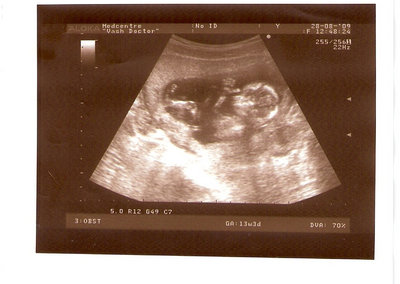

СЫН

| Вложения: |

2.jpg [ 110.14 КБ | Просмотров: 2304 ]

13 НЕД И 5 ДНЕЙ

3.jpg [ 96.81 КБ | Просмотров: 2302 ]

Nikisa писал(а): Foto prosto chudesnoe. A na kakom sroke uznali, chto sin.............. НА 13 НЕДЕЛЯХ.КАК РАЗ ВОТ В ЭТО узи, ОНО УМЕНЯ ВТОРОЕ БЫЛО. ЭТО КОНЕЧНО МАЛЕНЬКИЙ СРОК ДЛЯ ОПРЕДЕЛЕНИЯ ПОЛА. НО Я ПОПРОСИЛА ВРАЧА(ЭТО КТСТАТИВ РОССИИ БЫЛО) ХОТЯ БЫ ПРЕДПОЛОЖИТЬ. ЕЙ ВСЁ ТАКИ УДАЛОСЬ РАССМОТРЕТЬ.НУ ВООБЩЕМ ЧЕРЕЗ НЕСКОЛЬ ДНЕЙ ПОЙДУ К ВРАЧУ, УЖЕ АМЕРЕКАНСКОМУ И УЗНАЮ ТОЧНО. К ТОМУ ВРЕМЕНИ У МЕНЯ БУДЕТ СРОК 18 НЕДЕЛЬ. ХОТЕЛОСЬ БЫ ПОСМОТРЕТЬ НА ДРУГИЕ ФОТО НА ЭТОМ СРОКЕ ИЛИ БОЛЬШЕ. ТАК ЧТО ВЫКЛАДЫВАЙТЕ, ЕСЛИ НЕ ЖАЛКО!